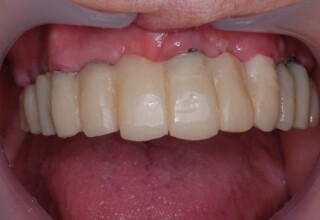

Ολική Στοματική Αποκατάσταση σε Εμφυτεύματα με διαφορετική προσέγγιση στην Άνω και Κάτω Γνάθο

Χρησιμοποιήθηκαν παλαιές χαμογελαστές φωτογραφίες της ασθενούς γιατί είχε χαθεί τελείως το φυσικό σχήμα των δοντιών εξαιτίας των πολλαπλών προσθετικών προσπαθειών που είχαν γίνει στο παρελθόν. Μεταφέρθηκε στην προσωρινή γέφυρα η σχέση των φυσικών δοντιών μεταξύ τους άλλα και με τα χείλη. Δοκιμάστηκε η φώνηση και η μάσηση με δυο διαφορετικές προσωρινές άνω γέφυρες και εκτιμήθηκε η αισθητική απόδοση τους. Αφού επιτεύχθηκαν σε βαθμό ικανοποιητικό η φώνηση και η αισθητική εμφάνιση της οδοντοφυΐας, η προσωρινή αποκατάσταση χρησιμοποιήθηκε ως οδηγός για την τελική.

Αρχικό

Ενδιάμεσο

Τελικό